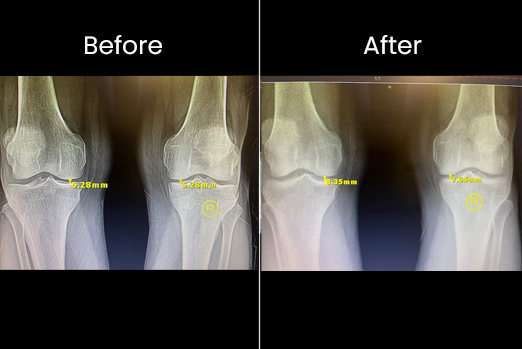

Even a small increase in personal space can have a significant impact on someone's life.

A little more space can make a big difference in a person's life.